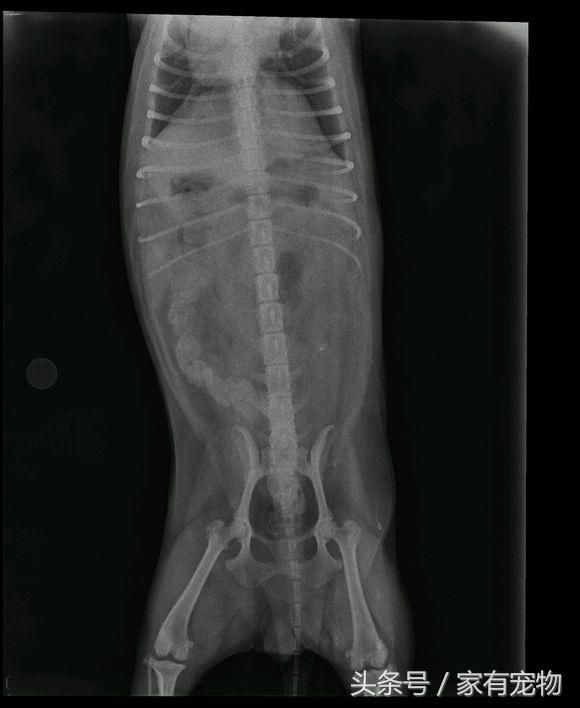

诊断:当患犬出现破行时,触诊整个患肢无痛觉,对出现明显破行者,用手检查髌骨可见明显脱位现象。在X光正位片可见髌骨位于股骨的内侧或外侧,而不在股骨滑车中,同时可见滑车沟变浅、胫骨近端弯曲转位和股胫关节成角异常。当幼犬的髌骨钙化不全时,其移位则很难显示;X光侧位片上可见髌骨不在滑车沟内而是与股骨髁重叠。